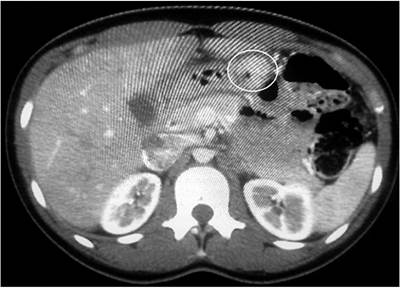

Se trata de un paciente masculino de 75 años que era consumidor crónico de IBP y en los estudios de control en esofagogastroduodenoscopia se evidenció un pólipo en la región antral hacia la curvatura menor que ya se encontraba en seguimiento endoscópico desde 2014 con la toma de una endoscopia más biopsias, todas hasta ese momento negativas para malignidad. En 2016 se evidenció la aparición de una nueva lesión polipoide, por lo que se realizó una USE cuyo resultado demostró una lesión sésil de 8 mm prepilórica que comprometía hasta la submucosa, y en la pared posterior del antro se encontró un pólipo hiperplásico sésil de 25 mm con compromiso hasta la submucosa (Figura 5). Durante este estudio se tomaron biopsias que reportaron pólipos hiperplásicos en la curvatura menor sin descartar compromiso tumoral en la base de los pólipos. Por dicha razón fue llevado a gastrectomía subtotal con vaciamiento ganglionar D2 por laparoscopia, y no se reportaron complicaciones en el posoperatorio.

Se trata de una mujer de 26 años que consultó por un cuadro de epigastralgia, con antecedente de dos hospitalizaciones previas por cuadros de hemorragia de vías digestivas altas y con una esofagogastroduodenoscopia de la última hospitalización que reportaba una lesión de 2,5 cm en el antro gástrico (con un reporte de biopsia compatible con GIST); además, se solicitaron imágenes tomográficas en la que se describió una lesión quística de 3 cm sobre la curvatura menor (Figura 6). Se llevó a una antrectomía radical por laparoscopia y en el intraoperatorio se evidenció una lesión prepilórica de 4 cm con presencia de ganglios de hasta 1 cm hacia la curvatura menor. Durante el posoperatorio presentó un cuadro de íleo, el cual se resolvió a los pocos días con manejo médico, y posteriormente fue dada de alta.

En el control por la consulta externa de cirugía, el reporte de la pieza quirúrgica evidenció un cistoadenoma mucinoso originado en tejido pancreático ectópico (Figura 7). Teniendo en cuenta que la transformación maligna es extremadamente rara, la paciente fue dada de alta por el servicio de cirugía.